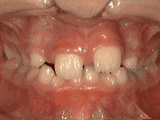

前牙移位多由于乳牙过早缺失导致,多因乳牙龋坏不及时治疗、意外断折引起。

牙齿错乱表现为多生牙、牙床过小等造成,严重的拥挤错乱一般需要拔牙,给余牙移动的空间。